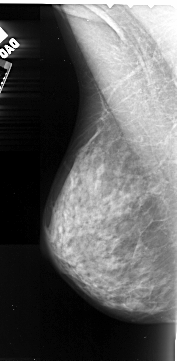

A_1057_1.LEFT_CC

LEFT_CC LINES 4201 PIXELS_PER_LINE 2326 BITS_PER_PIXEL 16 RESOLUTION 42 NON_OVERLAY

FILE: A_1057_1.RIGHT_CC.OVERLAY

TOTAL_ABNORMALITIES 1

ABNORMALITY 1

LESION_TYPE MASS SHAPE OVAL MARGINS ILL_DEFINED

ASSESSMENT 4

SUBTLETY 4

PATHOLOGY MALIGNANT

TOTAL_OUTLINES 1

BOUNDARY